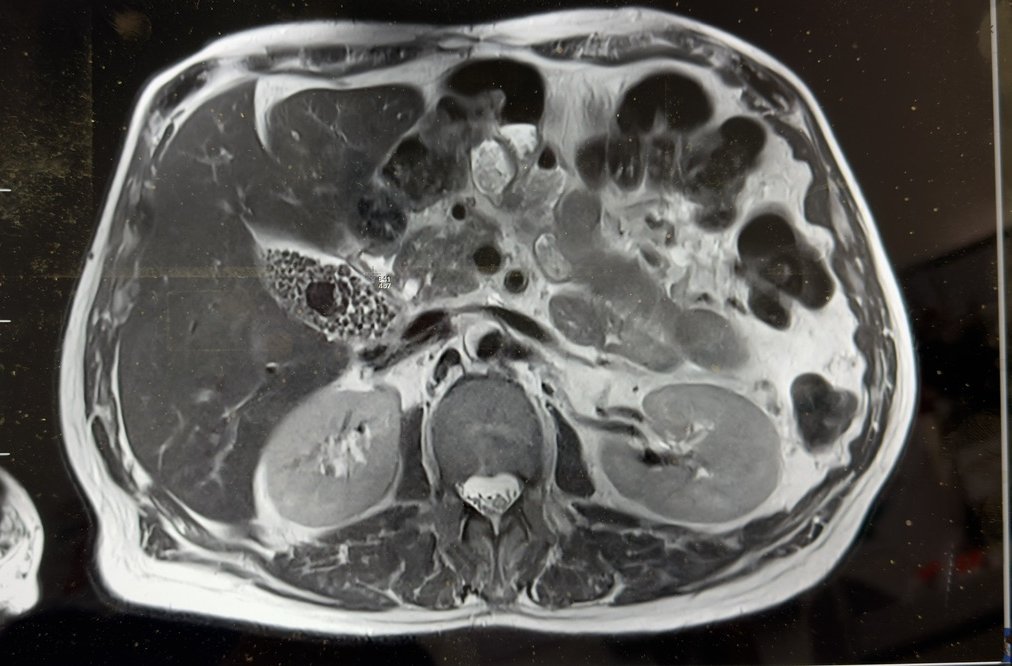

Example images (de-identified, illustrative)

These are examples from a real case. They are included for education only and are not for diagnostic use.

MRI axial slice showing gallbladder filled with multiple stones

MRI (axial): gallbladder packed with multiple stones, including one larger stone.